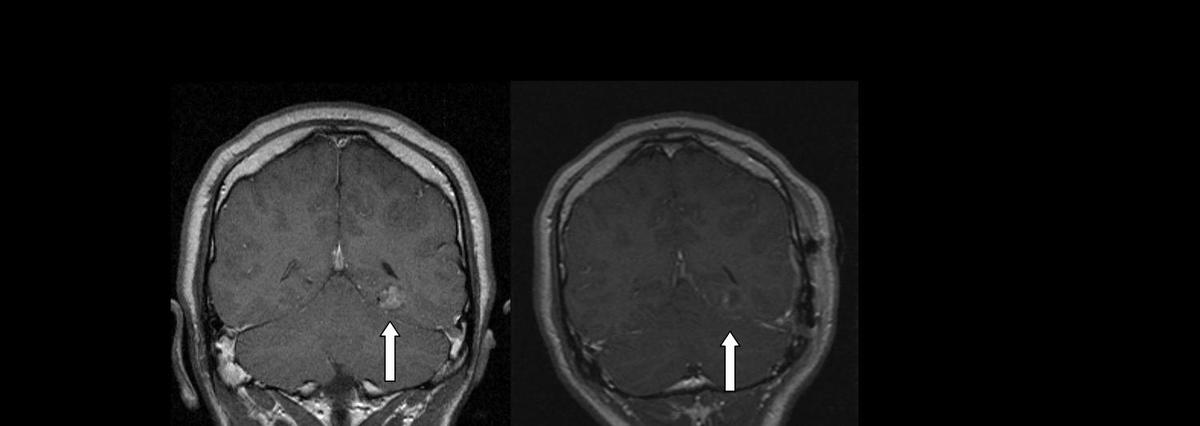

Lesionectomy image (before and after)